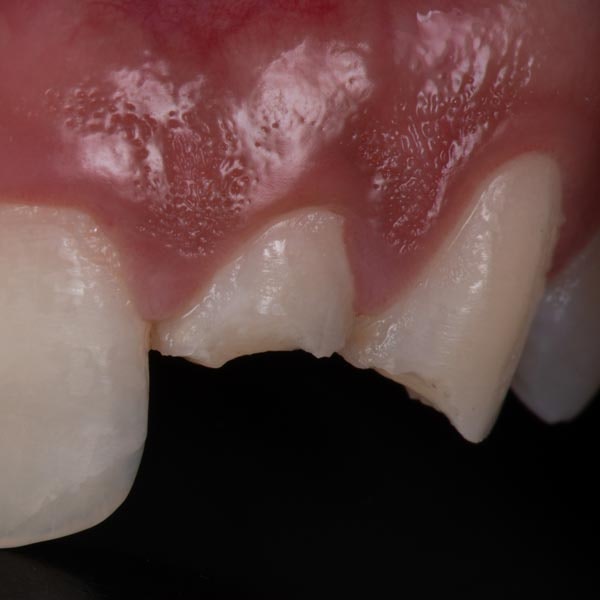

Do I Need a Tooth Extraction?

Severe pain, gum swelling, and visible tooth fractures can all be indicative of a serious dental problem. However, there is no way to know for sure if you need extraction unless you see a dentist for an exam.